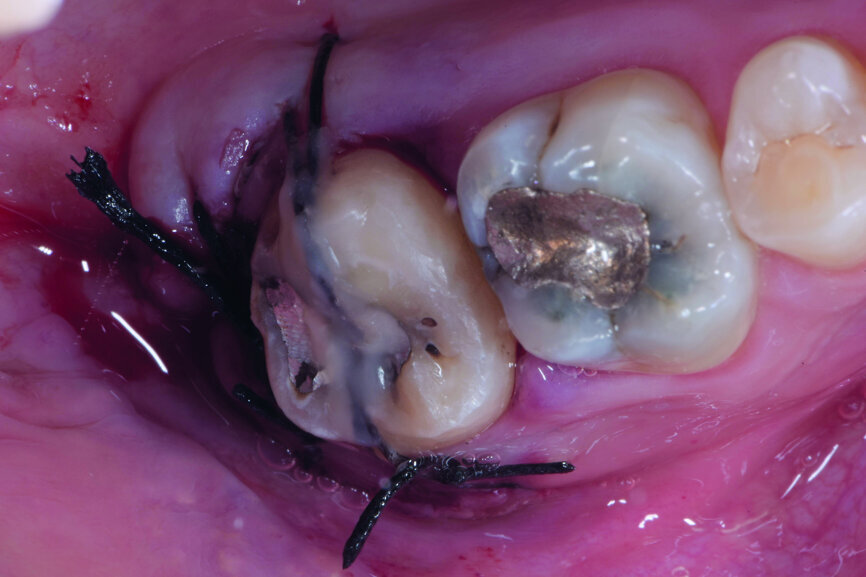

Fig. 8: Transplanted tooth sutured, immediately after surgery.

After local anaesthesia with 2 per cent mepivacaine with 1:100,000 adrenaline, the right maxillary second molar was atraumatically extracted. Initially with a size 15c surgical blade, the periotomy was realised and then the tooth was extracted after separating the roots to avoid unnecessary trauma to the alveolar bone. Then the donor right maxillary third molar was extracted after periotomy as described and transplanted into the adjacent site. Because of the slight differences in the root anatomy, it was necessary to remove the intraradicular bone septum of the receiving site to al- low tooth positioning, and a odontoplastic of the donor tooth crown was performed to maintain it not in occlusion. An antibiotic (amoxicillin/clavulanic acid, 1 g, by mouth twice a day for five days) was prescribed, along with rinses with 0.2 per cent chlorhexidine. The tooth was keep stable with sutures (Fig. 8). A periapical radiograph was taken (Fig. 9). At the suture removal at two weeks, the tooth showed good stability, and positive adaptation of the soft tissue was observed (Fig. 10). At four weeks, the tooth was stable and the soft tissue looked healthy (Fig. 11). The patient did not show any adverse effects and stated that the tooth was fully functional. Examination of the avulsed second molar showed the extent of the perforation (Figs. 12 & 13).